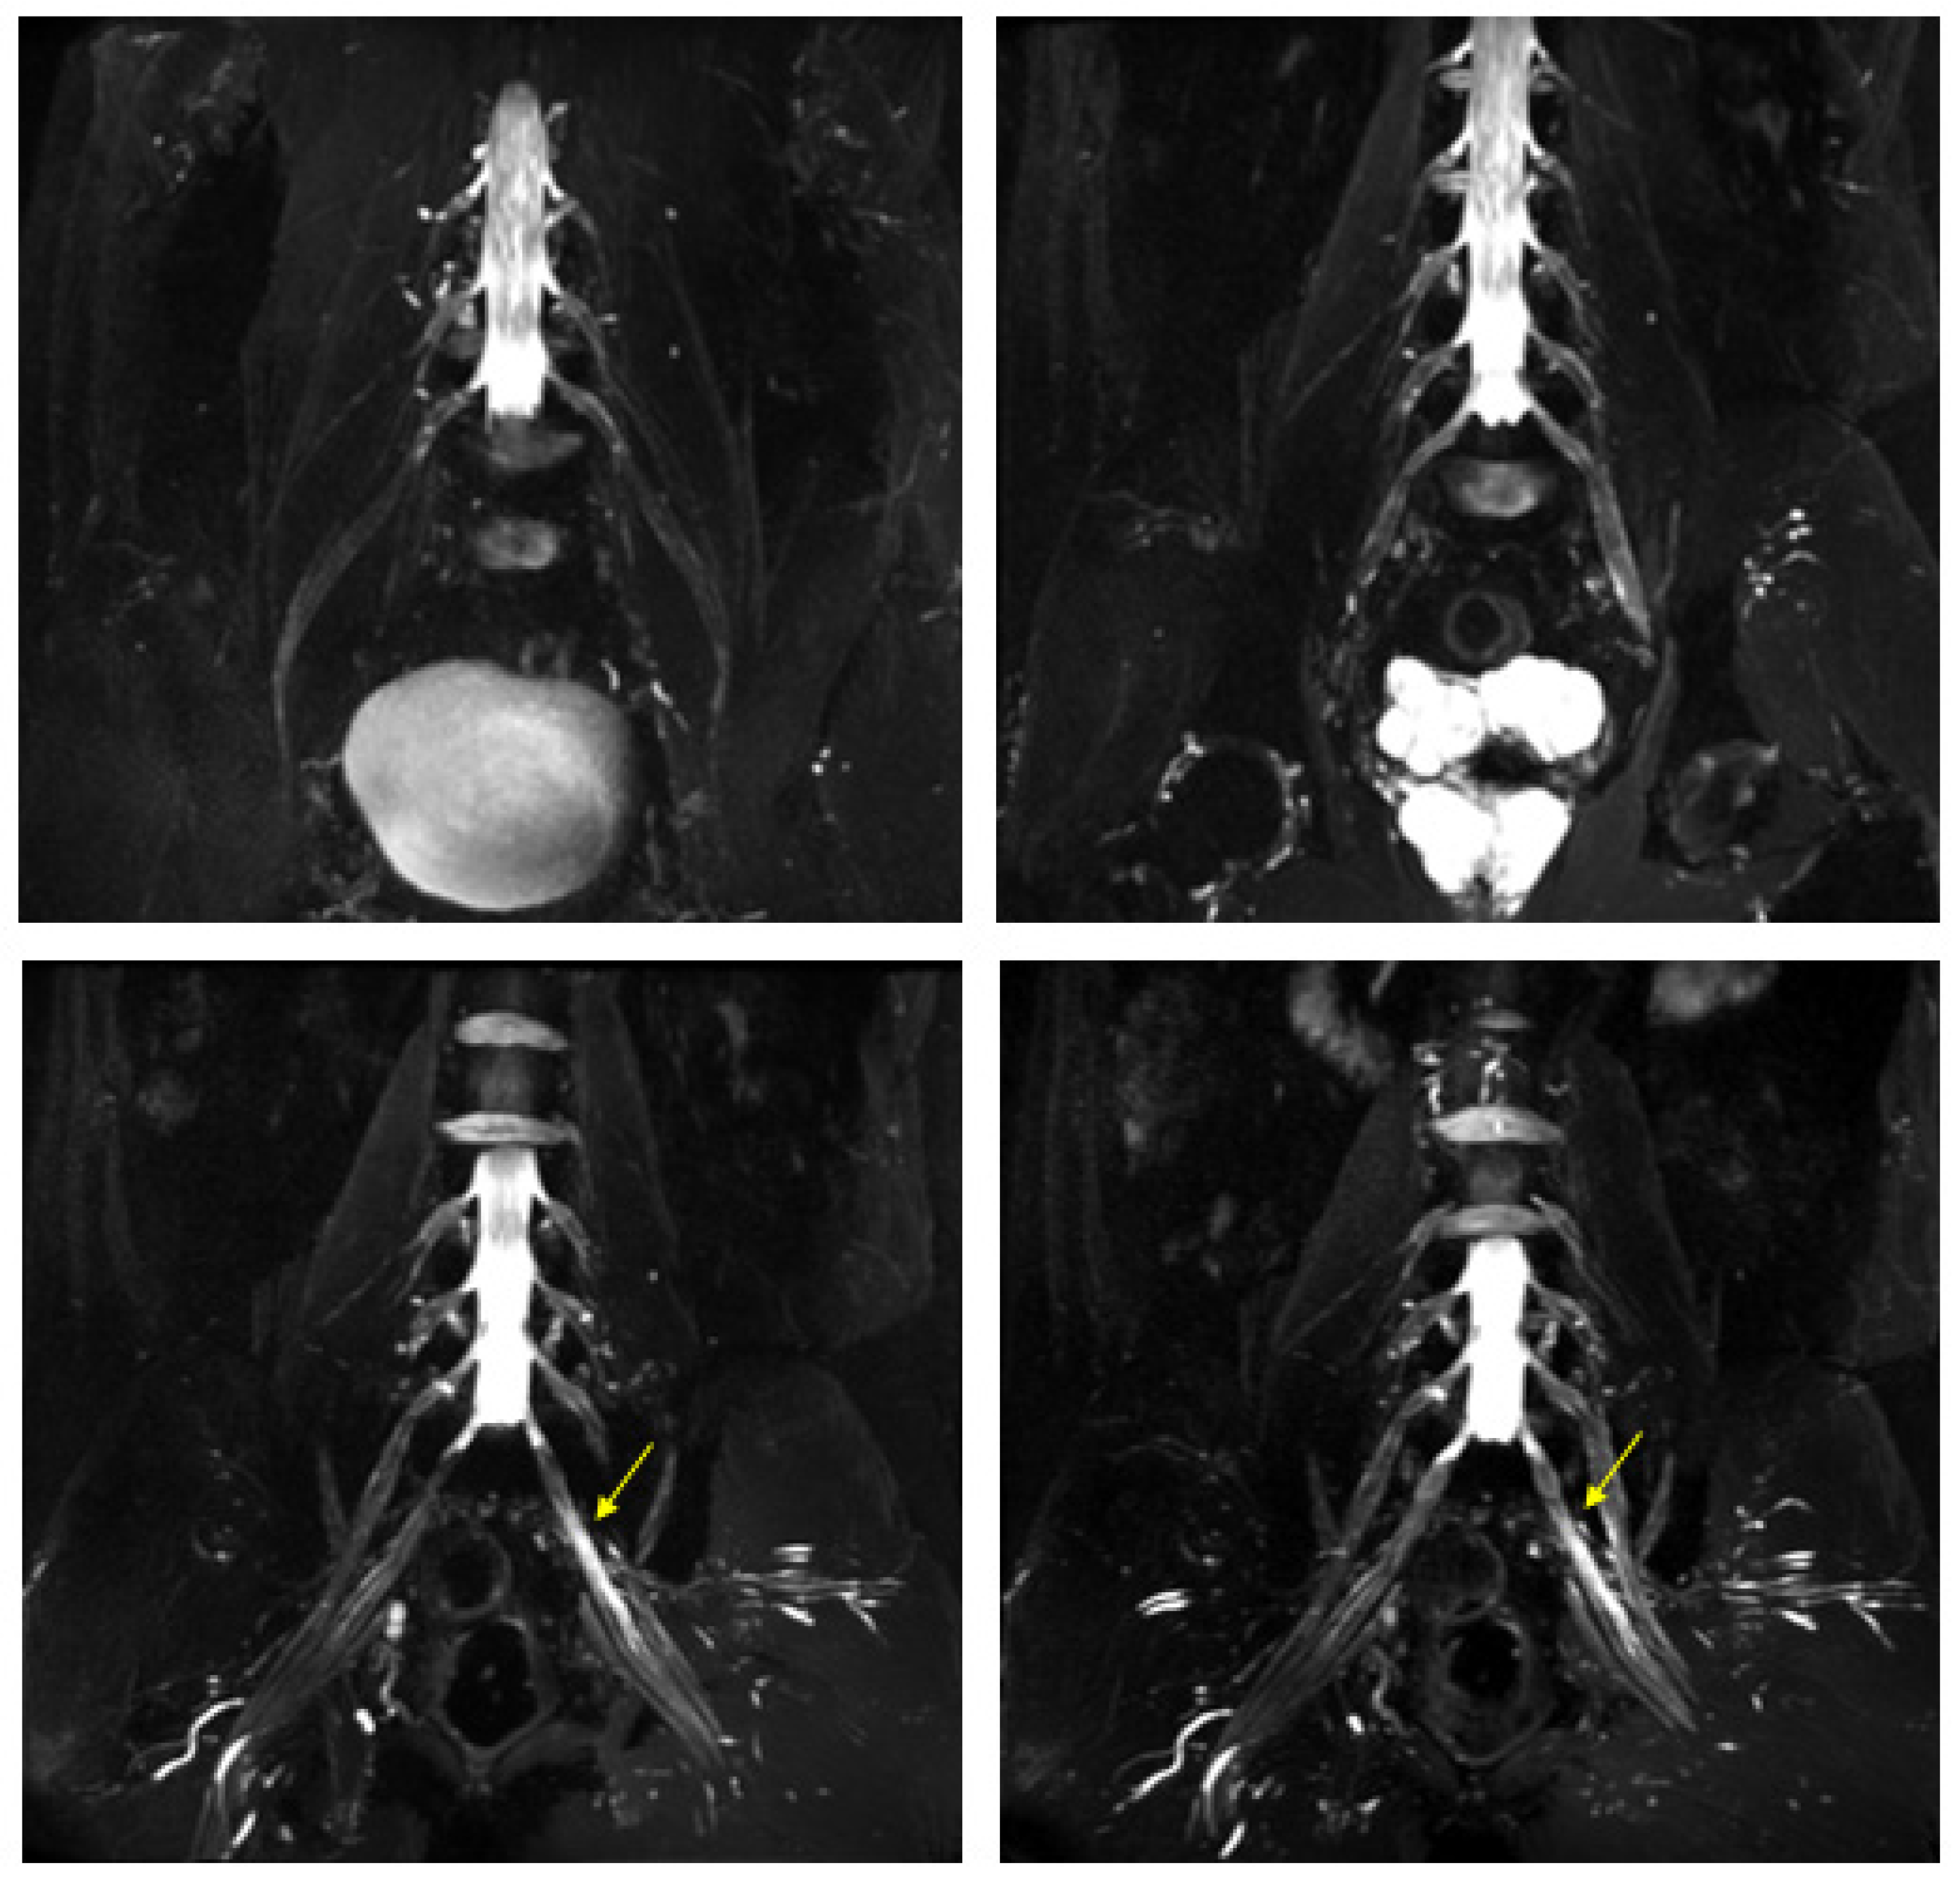

Lumbar Plexus Images . Mrn images in coronal stir 3d space (c) demonstrate lumbar plexus trunk thickening (arrowhead). The lumbar plexus gives rise to several branches which supply various muscles and regions of the posterior abdominal wall and lower. Mrn images in axial t2. An image of the lumbar plexus with its nerves highlighted in yellow. The lumbar plexus is a complex neural network formed by the lower thoracic and lumbar ventral nerve roots (t12 to l5) which supplies. Creating your own cases is easy. Schematic of the lumbar plexus. Use them in multiple choice question;

Lumbar Plexus Images Mrn images in coronal stir 3d space (c) demonstrate lumbar plexus trunk thickening (arrowhead). The lumbar plexus gives rise to several branches which supply various muscles and regions of the posterior abdominal wall and lower. Mrn images in axial t2. Mrn images in coronal stir 3d space (c) demonstrate lumbar plexus trunk thickening (arrowhead). Use them in multiple choice question; Creating your own cases is easy. The lumbar plexus is a complex neural network formed by the lower thoracic and lumbar ventral nerve roots (t12 to l5) which supplies. Schematic of the lumbar plexus. An image of the lumbar plexus with its nerves highlighted in yellow.